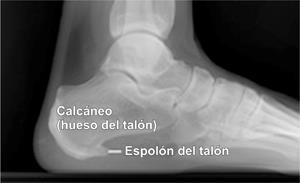

Plantar fasciitis is a painful inflammation of the plantar fascia, a fibrous band of tissue on the bottom of the foot that helps to support the arch.

What Kind of Feet Do I Have â" Everything You Should Know from onyourleg.com To revisit this article, visit my profile, thenview saved stories. If you have persistent pain in your foot that mainly affects the arch or the heel, you might have plantar fasciitis. Request an appointment using our secure online form. The pain occurs when the plantar fascia, the tissue that connects the heel bone to the toes, becomes weak or i. The problem occurs when the plantar fascia, a band of tissues on the bottom of the foot that extends from your heel to your toes, becomes inflamed. Webmd shows you what you can do to feel better. Get the latest news and events plantar fasciitis is a common condition that causes heel pain. This is a condition in which your plantar fascia, a ligament in your foot that connects your toes to your heel, tightens up.

Plantar fasciitis is a painful inflammation of the plantar fascia, a fibrous band of tissue on the bottom of the foot that helps to support the arch. Enter search terms and tap the search button. We researched different options to help you choose. We researched the best men's running shoes for plantar fasciitis. Does the sharp pain come back after you sit or stand for a while? Do your feet hurt when you take those first steps in the morning? To revisit this article, visit my profile, thenview saved stories. Plantar fasciitis is an inflammation of the tissue in the foot used for walking. The best men's shoes for plantar fasciitis stay supportive through many miles of wear and tear. The pain occurs when the plantar fascia, the tissue that connects the heel bone to the toes, becomes weak or i. The plantar fascia is tissue that runs along the bottom of your foot. Here are the five best women's cross training shoes. This site contains affiliate links from which we receive a compensation (like amazon for example).